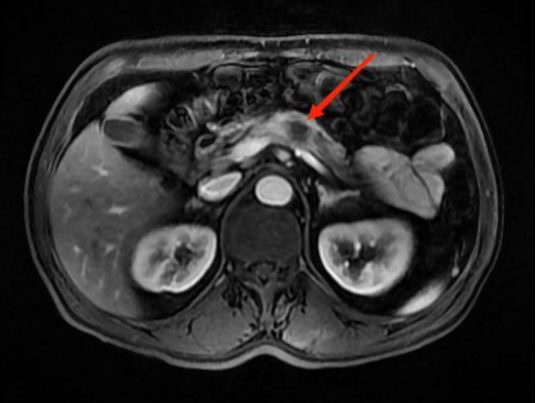

图4A

图4B

图4C

图4D

典型病例4:

男性,59岁,间断左中上腹部疼痛2个月,为隐痛,程度较轻,伴夜间痛。图A:T1WI示胰腺体部见团片状稍低信号影,边界不清。图B:增强扫描示病灶呈弱强化。图C:胰腺体尾部实质萎缩。图D:MRCP示远端胰管扩张。